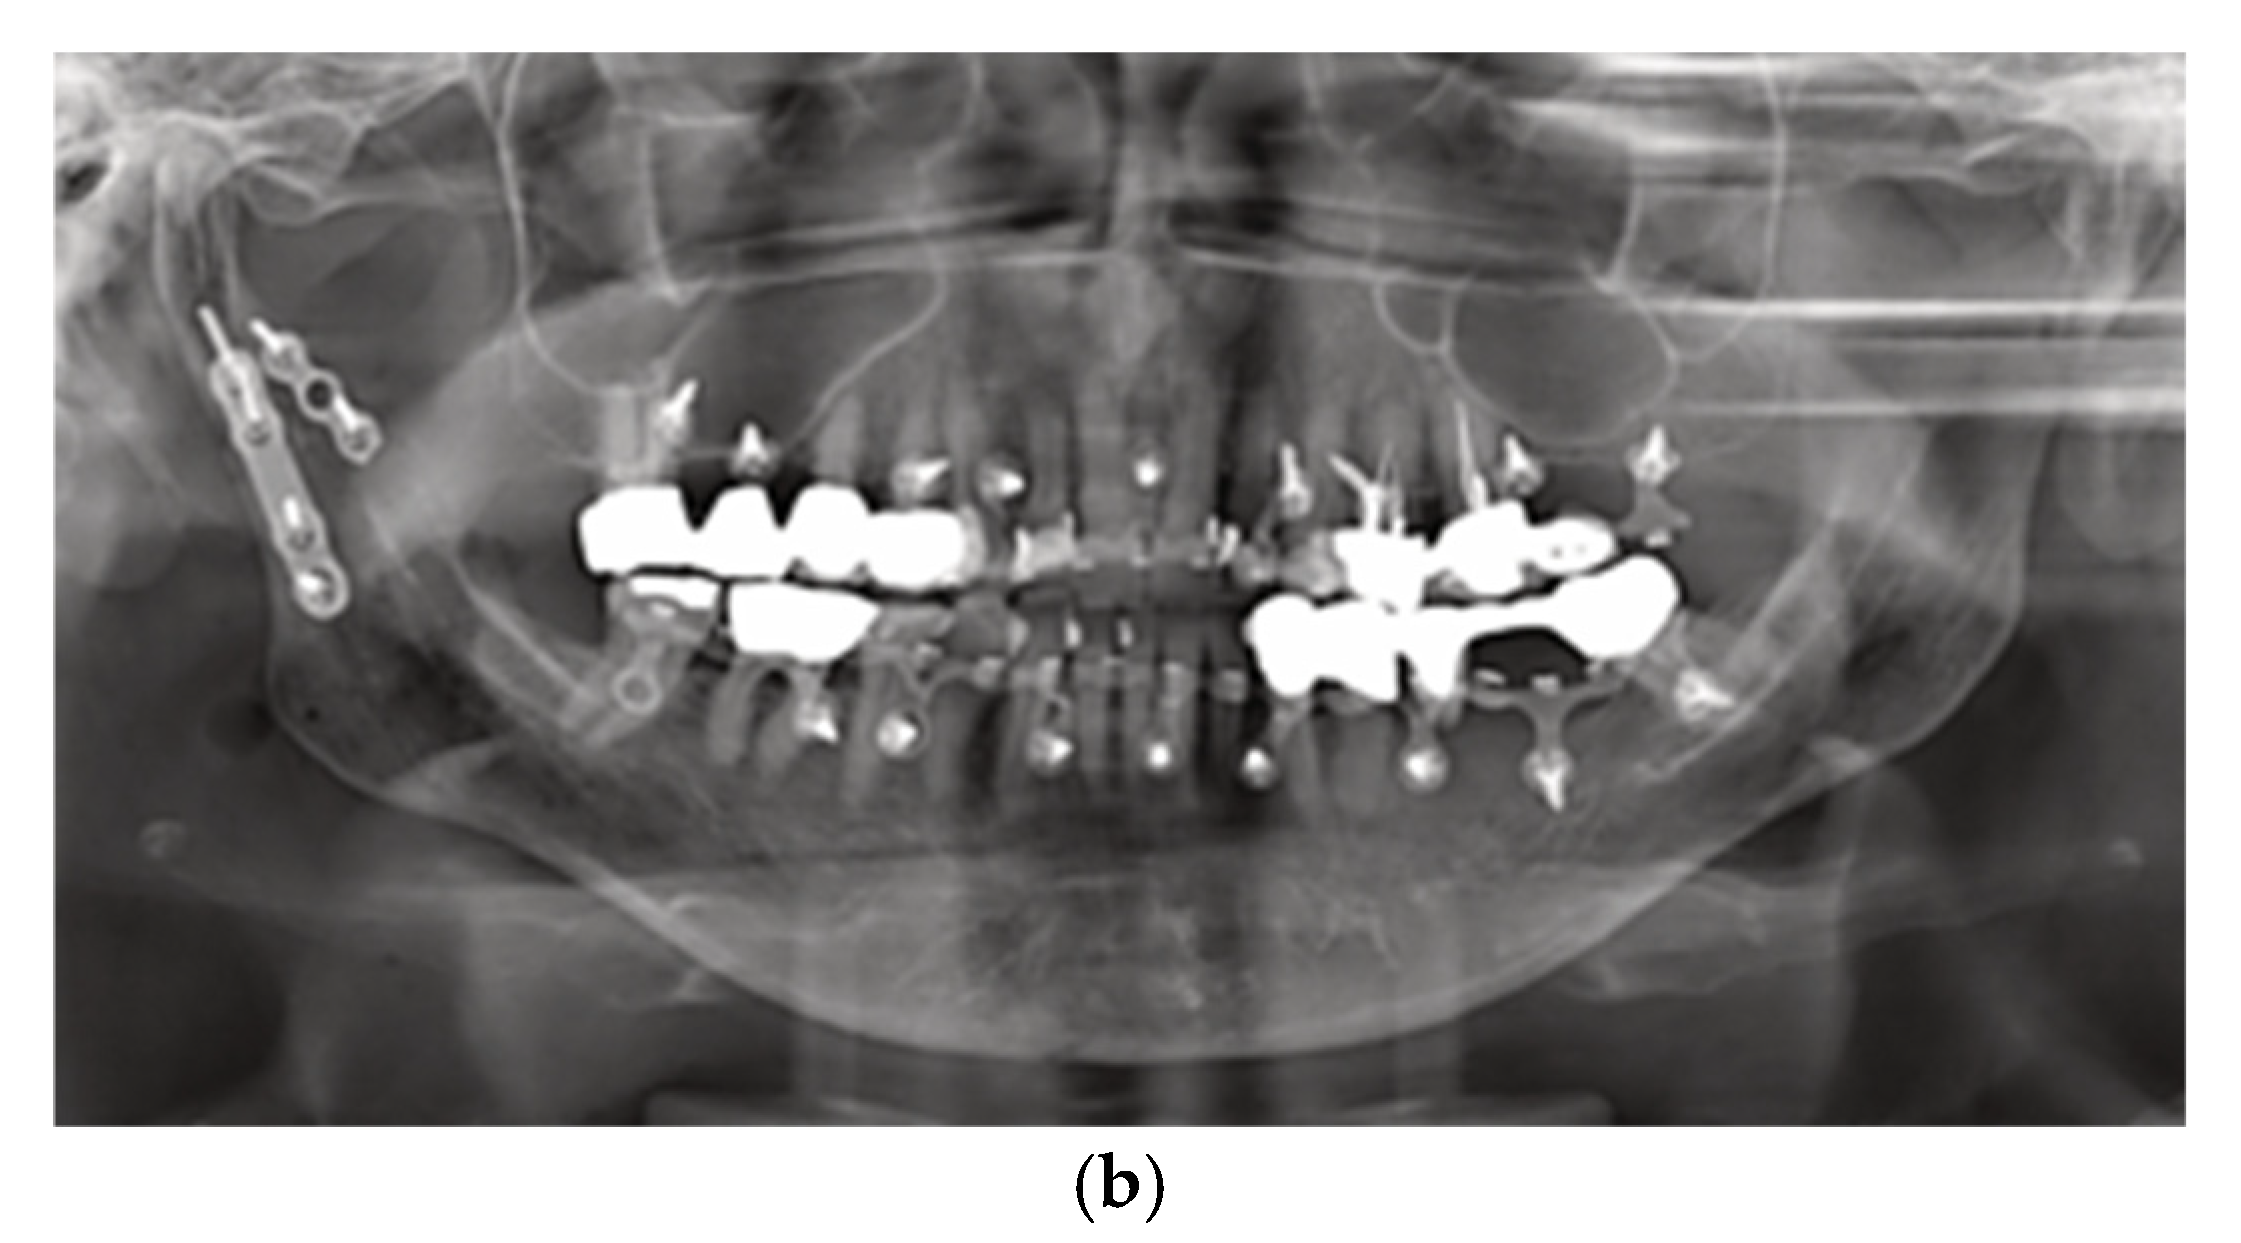

4.13. Transoral ORIF – Vestibular Incision Placement